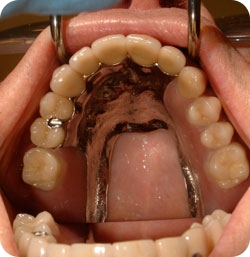

The abutment used to support dentures and partials is different from those that support crowns or bridges. These abutments connect via a replaceable nylon insert to a housing imbedded in the denture or partial. These inserts can be changed to increase the retention (or the amount of force it takes to remove the denture) or if the insert has become worn with time. This arrangement makes the prosthesis very serviceable and significantly extends its lifespan.